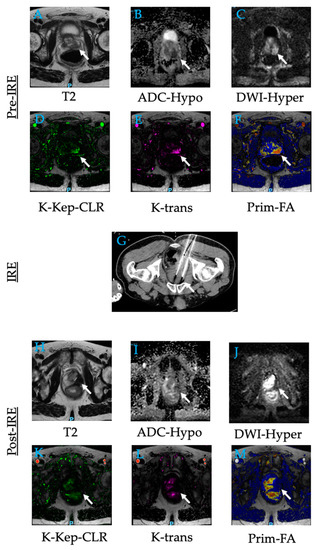

3.4. Irreversible Electroporation

9. Prostate Tumors